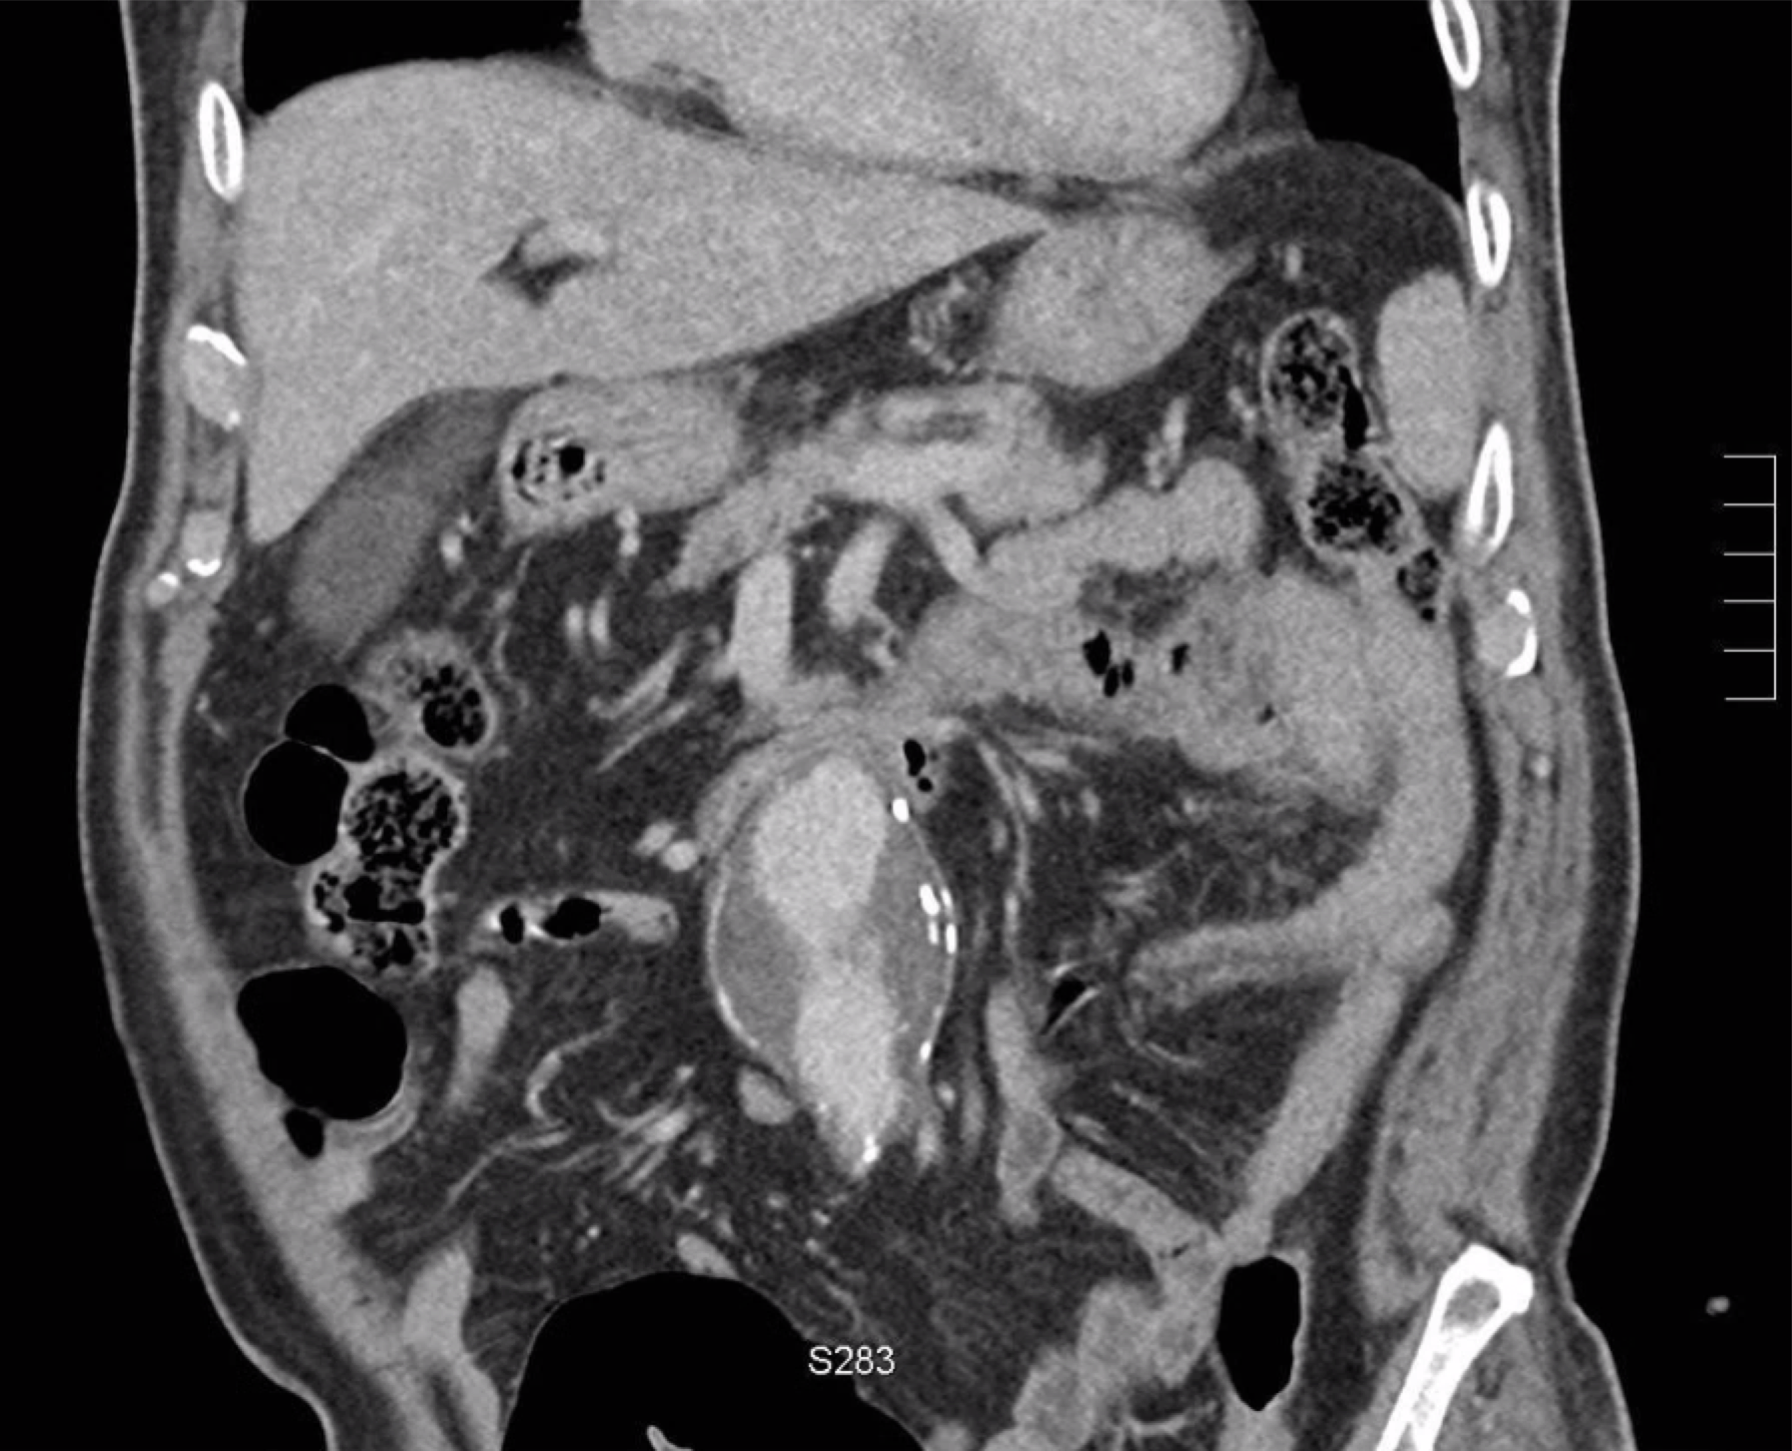

large abdominal aortic an.